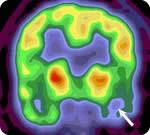

Single Photon Emission Computed Tomography (SPECT) scan is a type of nuclear imaging test that shows how radioactive tracers flow to tissues and organs. In epilepsy, this test is used to look at how the blood flows through the brain. The SPECT scan shows changes in blood flow during or in-between a seizure. This information can show doctors information about the location of seizures and whether they are contained in certain areas of the brain.

- Ictal SPECT scans occur during the epileptic seizure. The image on the left shows blood flow during a seizure and the one on the right shows blood flood between seizures.

- Inter-Ictal SPECT scans occur between seizures.

The nuclear medicine doctor will review the scan to determine where the seizure is coming from and compare both the Ictal and Inter-Ictal SPECT scans. Pictures from your scan may show bright spots that tell the doctor what areas of the brain have absorbed more of the radioactive tracer and give rise to where the seizures are coming from. This information will be passed on to your epilepsy team and you should have some preliminary results before being discharged from the EMU. Further information will be provided at the next follow-up appointment with your epileptologist.

The arrow points to where the seizures are coming from. The area is damaged and, between seizures, uses less energy. During the seizure, it uses more energy.